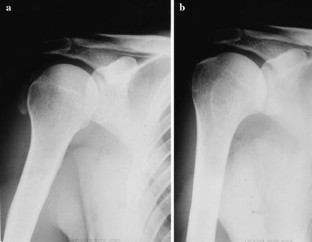

Fig. 1